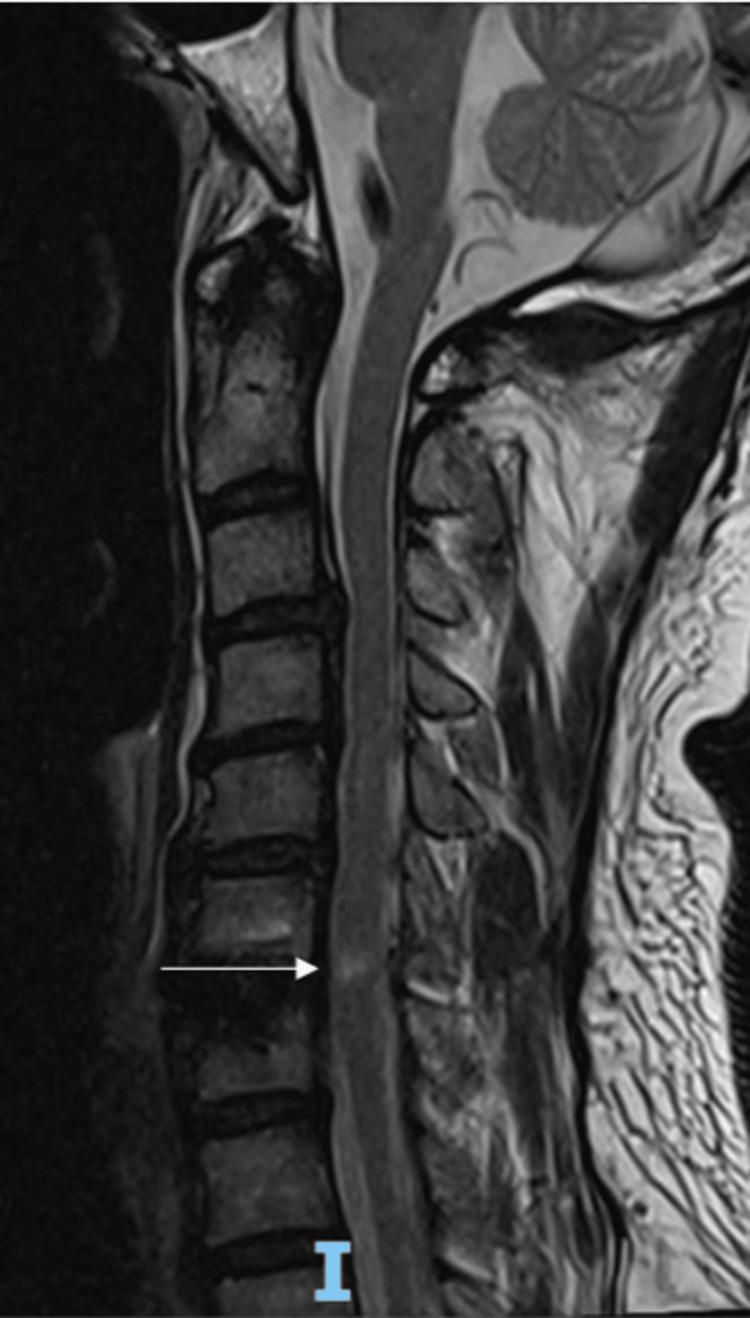

Spinal cord reperfusion injury following decompressive surgery is extremely rare. This complication is known as white cord syndrome (WCS). A 61-year-old male presented with chronic neck stiffness associated with left C6/C7 radiculopathy and numbness. Magnetic resonance imaging (MRI) of the cervical spine reported a severely narrowed left C6/C7 neural exit canal. C6/C7 anterior cervical decompression and fusion (ACDF) was performed. There was no significant intraoperative injury. On postoperative day 6, the patient developed bilateral C8 numbness, which started post-operation. He was treated for surgical site inflammation and was prescribed prednisolone and amitriptyline. However, his condition progressively worsened. At postoperative six weeks, there was right hemisensory loss, right triceps atrophy, and positive right Lhermitte's and Hoffman's tests. This subsequently progressed to right C7 weakness and bilateral lower limb radiculopathy at postoperative eight weeks. Postoperative MRI of the cervical spine revealed a new focal gliosis/edema within the spinal cord at C6/C7. The patient was treated conservatively with pregabalin and was referred for rehabilitation. Early diagnosis and treatment initiation are crucial in the management of WCS. Surgeons should be aware of this potential complication and counsel patients on the risk prior to surgery. Magnetic resonance imaging (MRI) remains the gold standard in the diagnosis of WCS. The current mainstay of treatment is high-dose steroids, intraoperative neurophysiological monitoring, and early recognition of postoperative WCS.

减压手术后的脊髓再灌注损伤极为罕见。这种并发症被称为白脊髓综合征(WCS)。一名61岁男性因慢性颈部僵硬伴左侧C6/C7神经根病和麻木前来就诊。颈椎磁共振成像(MRI)报告显示左侧C6/C7神经出口管严重狭窄。进行了C6/C7颈椎前路减压融合术(ACDF)。术中无明显损伤。术后第6天,患者出现双侧C8麻木,术后开始出现。他接受了手术部位炎症治疗,并开具了泼尼松龙和阿米替林。然而,他的病情逐渐恶化。术后六周,出现右侧半身感觉丧失、右侧肱三头肌萎缩以及右侧莱尔米特征和霍夫曼征阳性。随后在术后八周进展为右侧C7无力和双侧下肢神经根病。颈椎术后MRI显示C6/C7脊髓内出现新的局灶性胶质增生/水肿。患者接受了普瑞巴林保守治疗并被转诊进行康复治疗。早期诊断和开始治疗在WCS的管理中至关重要。外科医生应意识到这种潜在并发症,并在手术前向患者告知风险。磁共振成像(MRI)仍然是WCS诊断的金标准。目前的主要治疗方法是大剂量类固醇、术中神经生理监测以及术后WCS的早期识别。